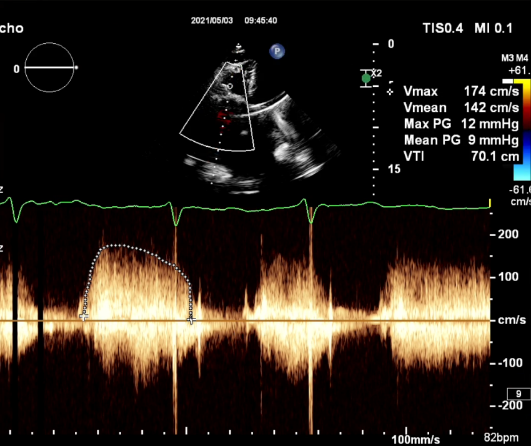

食道超声评估

三尖瓣术前平均压差9mmHg

术前TTE-TV生物瓣狭窄